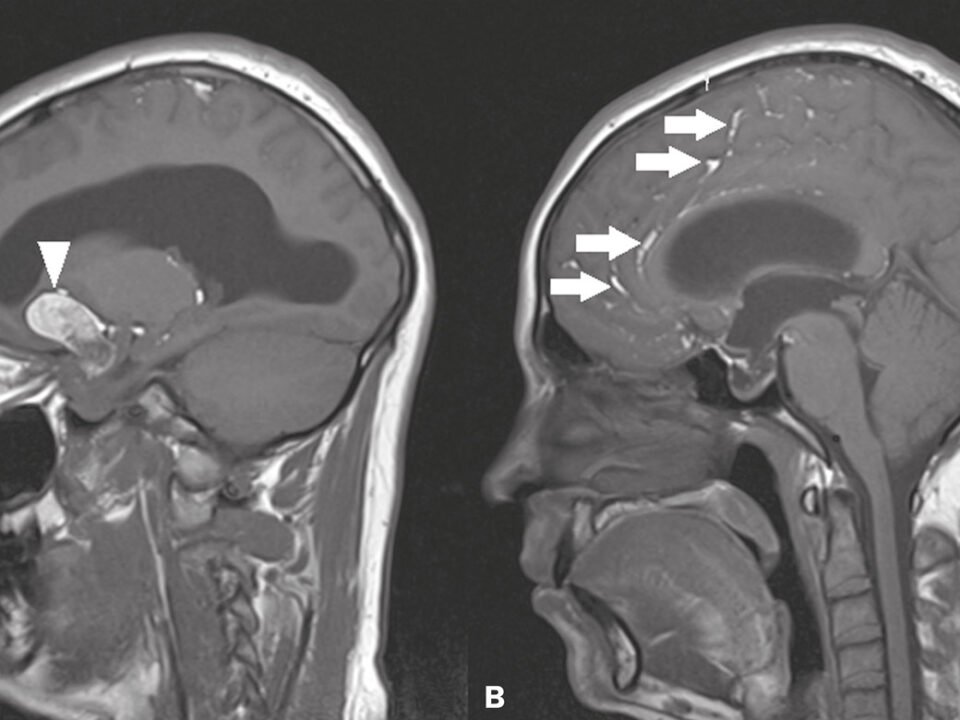

Cistos Cerebrais

➤ O que são? Cistos cerebrais são cavidades preenchidas por líquido que se formam dentro ou ao redor do cérebro. Ao contrário dos tumores, eles não […]